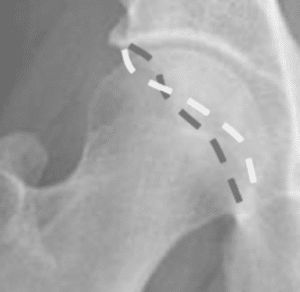

Причиной этого синдрома является врожденный удар кости или несчастный случай, так что головка бедренной кости не попадает в правую полость в идеале, чтобы позволить ей свободно двигаться. В случае любого движения, которое ударяет расширение полости, хрящ повреждается, и сустав может быть разрушен, как показано на следующих рисунках.

При лечении бедренно-ацетабулярного поражения преимущественно артроскопические методы лечения находятся на переднем плане. Это делайтся с помощью 2-4 небольших разреза и специальных инструментов для удаления костных насадо, чтобы тазобедренный сустав на всех 3 уровнях мог продолжать выполнять полное движение, не вызывая механических проблем и боли.

Артроскопическое удаление впадины с новым контуром перехода головы и шеи.